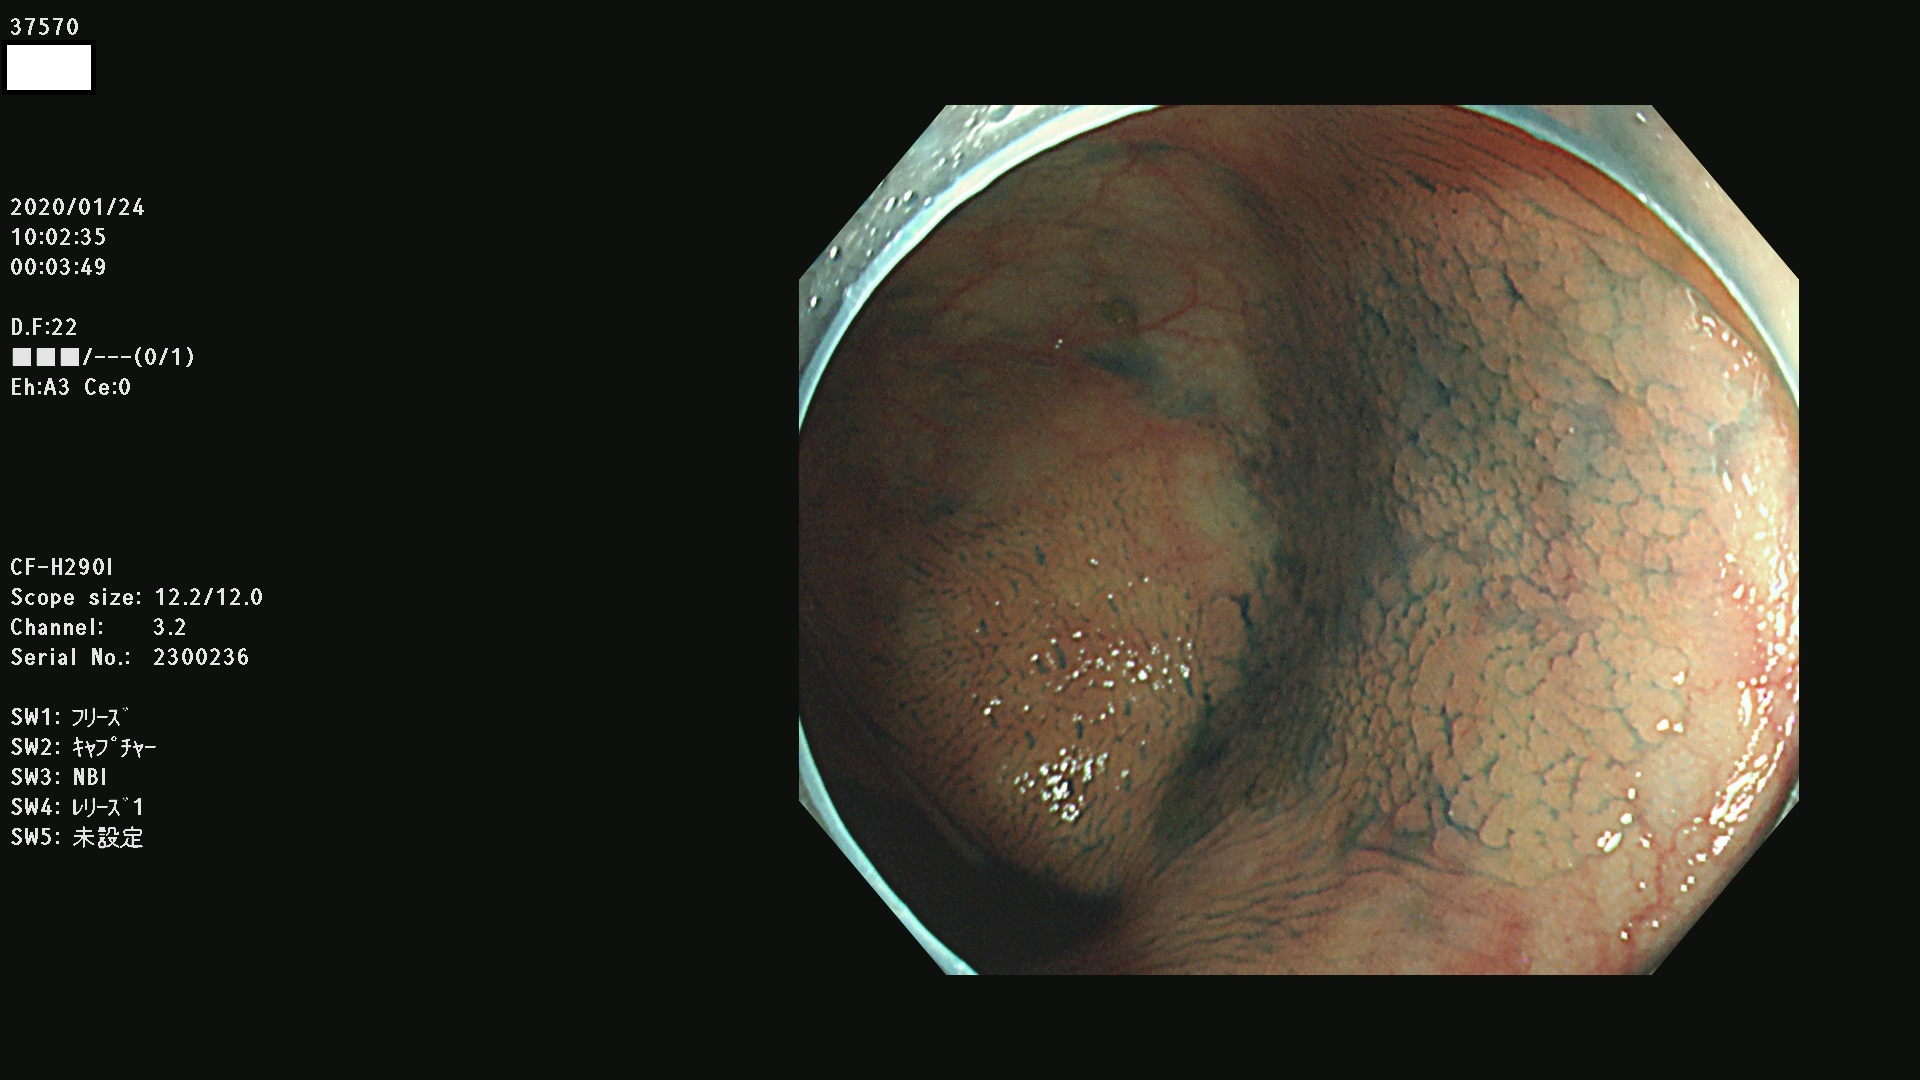

発見困難で危険性の高い平坦型病変(上記100名より抽出) ![]()